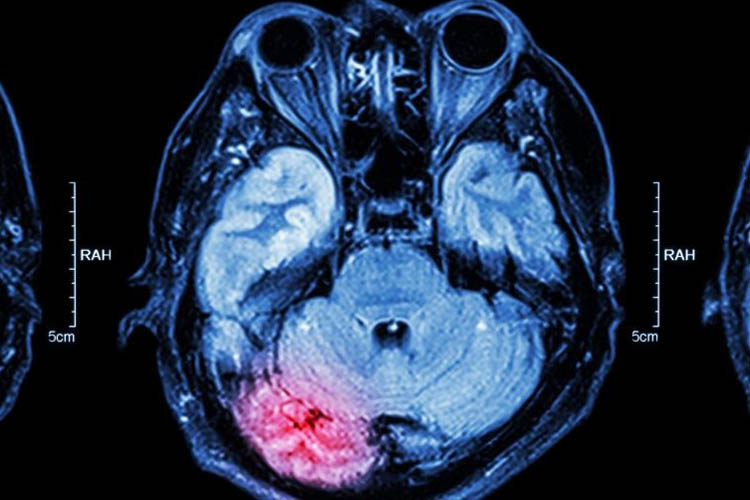

«Siamo stati in grado di applicare in modo efficiente questo trattamento in contesti di emergenza ed è stato ben tollerato» riferiscono. «Inoltre, i pazienti che hanno ricevuto un trattamento attivo hanno mostrato un miglioramento promettente, misurato osservando le scansioni cerebrali dopo il trattamento».

I ricercatori hanno anche valutato i biomarcatori di imaging di neuroprotezione e miglioramento collaterale a 2-4 ore e 24-30 ore dopo la stimolazione (punti temporali precoce e tardivo, rispettivamente).

La regione ipoperfusa è stata ridotta di una mediana del 100% (dal 46% al 100%) nel gruppo attivo, ma è aumentata del 325% (dal 112% al 412%) nel gruppo sham. La variazione quantitativa relativa del volume ematico cerebrale nella post-stimolazione precoce era pari a una mediana del 64% (dal 40% al 110%) nei pazienti attivi contro il -4% (da -7% a 1%) nei pazienti sham e «seguiva un modello dose-risposta».

Nel gruppo C-tDCS attivo, il recupero mediano della penombra ischemica è stato del 66% (dal 29% all’80,5%) rispetto allo 0% (IQR da 0% a 0%) nel gruppo sham. Questi risultati «indicano un possibile, vero effetto biologico del trattamento» sostengono Bahr-Husseini e coautori.